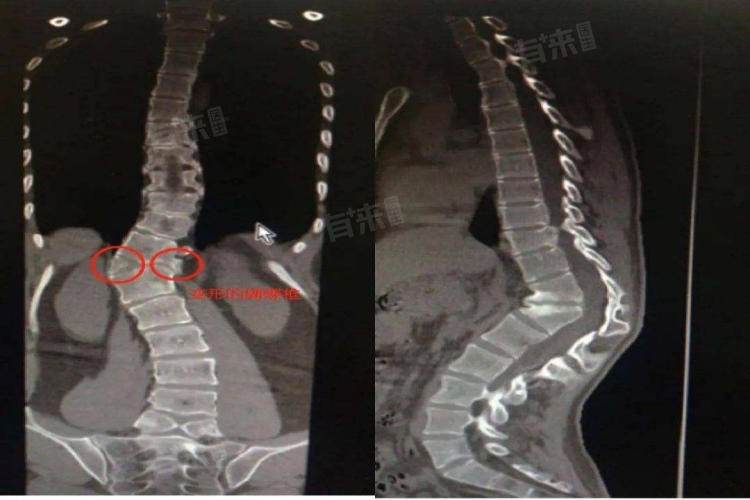

- 小儿骨科:该科室医生专注于儿童骨骼肌肉系统疾病,擅长对宝宝脊柱突出进行初步诊断。通过详细的体格检查,评估脊柱外观形态、活动度及是否存在压痛等症状;借助X线、CT等影像学检查,判断脊柱骨骼结构是否存在异常,如椎体畸形、骨折等,从而明确病因,制定针对性治疗方案,包括保守治疗或手术干预建议。

- 脊柱外科:若宝宝脊柱突出病情复杂,涉及严重的脊柱畸形或需手术治疗,脊柱外科是专业选择。脊柱外科医生在脊柱手术方面经验丰富,能够开展复杂的脊柱矫形、减压融合等手术。他们通过进一步的影像学评估和专业分析,确定手术可行性和具体方案,旨在恢复脊柱正常解剖结构和功能,解决因脊柱突出引发的严重问题。